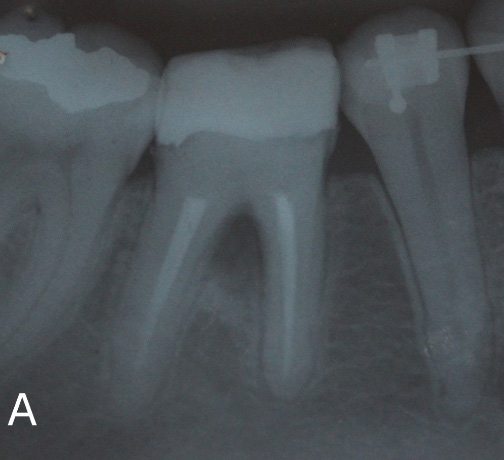

Strategies for endodontic retreatment

Read article